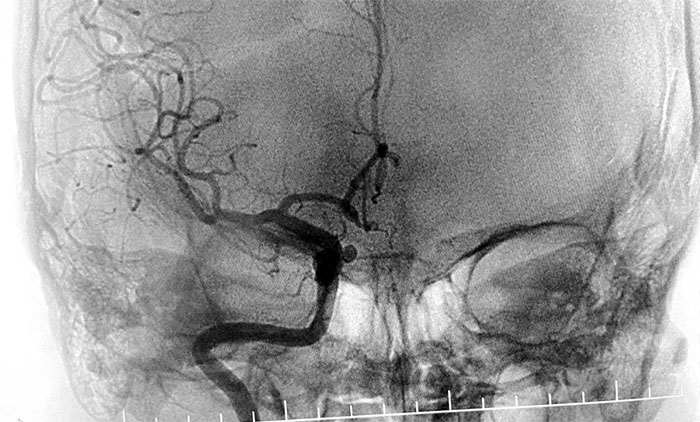

患者入院后,余志良主任为患者完善查体,根据病情特点,着重排查脑血管疾病可能。通过CTA检查,发现右侧颈内动脉C6段动脉瘤。医院学术副院长、神经内科4A病区主任席刚明教授团队进一步行DSA脑血管造影检查,提示右颈内动脉眼动脉段动脉瘤。

▲ DSA检查提示,右颈内动脉眼动脉段动脉瘤

通过审慎讨论评估,余志良主任和席刚明教授一致认为,该部位动脉瘤可因压迫重要血管神经,引起头痛头晕、视觉障碍等相关症状。一旦发生破裂出血,可导致患者出现一系列严重的神经功能损害,甚至危及生命。